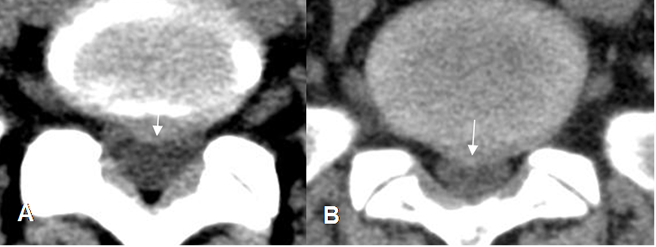

Fig 95. Hernia mediana.

A y B: TAC axial. Prominencias asimétricas, a nivel central que comprimen el saco dural.

Fig 96. Hernia mediana.

A y B: RM axial en T2. Prominencias asimétricas, a nivel central que comprimen el saco dural.